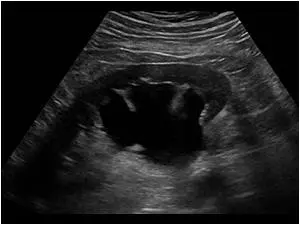

- сечокам’яна хвороба (камені в нирках)

Нирки мають бобовидную форму, з рівними контурами, чіткими межами, капсула повинна бути не ущільнена. Паренхіма товщиною в середньому сегменті 12-20мм, корти-медулярная диференціація і диференціація паренхіма-нирковий синус збережена. Ехоструктури центрального комплексу однорідна, гіперехогенна, чашечно-лоханочная система не розширена, конкрементів не містить.